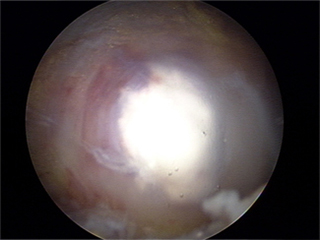

관절경 수술 전